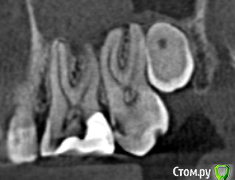

redgoldindigo Опубликовано 18 октября, 2019 Поделиться Опубликовано 18 октября, 2019 Здравствуйте. Меня замучила зубная боль, к своему стоматологу доверия нет, поэтому решила сделать КТ. Если кто может помочь в его расшифровке, буду благодарна. Может быть по скриншотам подскажете, это глубокий кариес или что-то еще? Ссылка на комментарий

krokomot Опубликовано 18 октября, 2019 Поделиться Опубликовано 18 октября, 2019 Большая вероятность что пульпа указанных зубов с пломбами инфицирована, требуется лечение. 1 Ссылка на комментарий